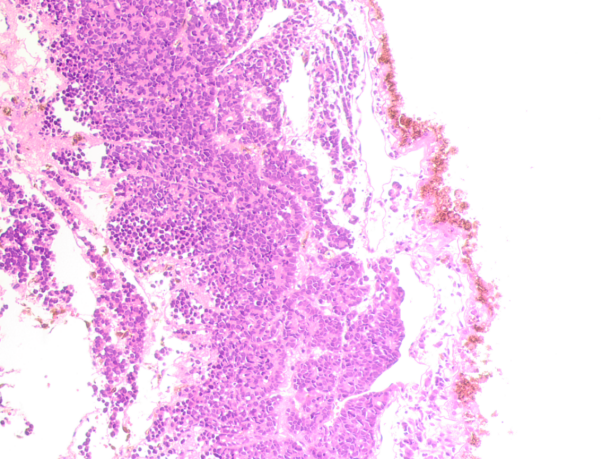

Figure 1 - Eye of a 9-year-old boy

Note: Retinoblastoma; Hematoxylin and eosin staining; Microphotograph; Magnification x100

The Ki-67 index, an index of proliferative activity expressed as a percentage, was 95% in the tumor structure, 42% in the tumor surroundings, and 1% in the marginal zone. Low index values in the tumor surroundings indicate a less aggressive malignancy and tumor growth process, but a high degree of aggressiveness in the structure of the Flexner-Wintersteiner rosettes. The classic Flexner-Wintersteiner rosette is a rounded cluster of cells grouped around a central lumen containing small cytoplasmic processes of the surrounding cells. The proliferative activity index demonstrated tolerance of the ocular structures to the treatment and the absence of an effective tumor response to conservative therapy. The data obtained predict rapid tumor growth and spread to all ocular structures, making eye extirpation the most appropriate strategy for stopping the malignancy. The evidence that Ki67-positive cells occupy the majority of the malignant tissue of Flexner-Wintersteiner rosettes, while the proliferative activity indices are lower at the periphery, does not contradict the data obtained by other authors that the malignancy process occurs against the background of possible partial differentiation of cells in the tumor zone towards photoreceptor cells. Electron microscopy performed by Karim M.M., Yamamoto M., Itoh H. (1996) showed that tumor cells forming the Flexner-Wintersteiner rosette have ultrastructural features of primitive photoreceptor cells . Transmission electron microscopy revealed the presence of large mitochondria on the luminal side of the cells forming the rosettes, which are presumably part of the inner segments of photoreceptor cells. The results of this study indicate a predominantly neuronal nature of neoplastic cells with differentiation characteristic of photoreceptors. Tajima Y., Munakata S., Ishida Y., et al. (1994) observed an increase in the number of long mitochondria and microtubules in the cell cytoplasm, indicating differentiation towards photoreceptors. The authors also noted that hereditary retinoblastoma demonstrated a higher degree of cell differentiation than the non-hereditary type. Differentiated photoreceptor retinoblastoma grew more slowly compared to undifferentiated retinoblastoma, so with the first variant, one can count on a cure with surgery . These observations allow us to draw additional conclusions about the biological nature of retinoblastomas. In addition, the cells in the rosette structure are stained in the same way as rods and cones, which allowed the authors to suggest that Flexner-Wintersteiner rosettes represent a special form of cellular differentiation of the retina. Flexner-Wintersteiner rosettes are characteristic not only of retinoblastomas, but also of pineoblastomas and medulloepitheliomas. Our data indicating that cells in the Flexner-Wintersteiner rosette structure, located in an area with a high concentration of Ki67-positive cells and undergoing irreversible mitosis, indicate a lack of differentiation and specialization of cells entering mitosis. The lumen filled with cells corresponding to blood cells indicates that Flexner-Wintersteiner rosettes in the vitreous body are formed due to angiogenesis and blood infiltration. When culturing retinoblastoma, Bogenmann E. and Mark C. (1983) consistently identified the spontaneous formation of well-differentiated Flexner-Wintersteiner rosettes, provided these structures were present in the patient's primary eye tumor .